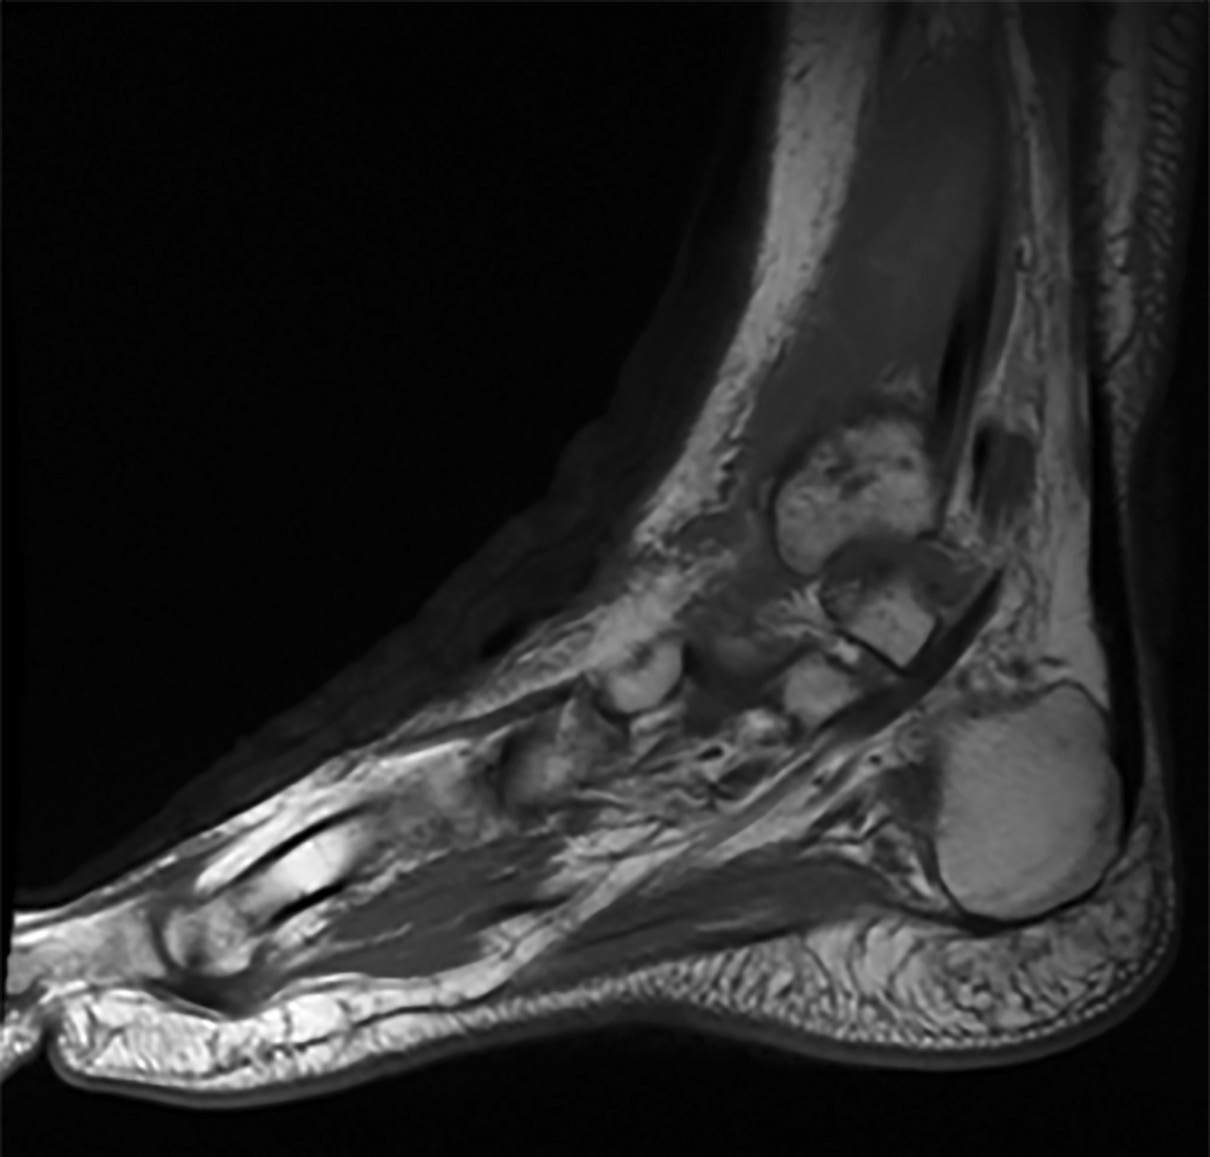

4. Рисунок 4. Магнитно-резонансная томография левого голеностопного сустава в режиме Т1. | |